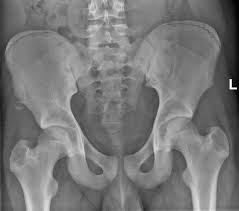

Anterior Superior Iliac Spine Hd Stock Images Shutterstock

Anterior Superior Iliac Spine Hd Stock Images Shutterstock from image.shutterstock.com

The coccyx is curved slightly forward, with its. It can be palpated by putting the hands at the top of the hipbones and following the bony margins toward the front of the hips. Outer lip of anterior iliac crest, anterior superior iliac spine (asis) insertion: Diagnosis is made with pelvis radiographs that shows an avulsion off the aiis. Jun 09, 2015 · at the posterior end of the ilium, the iliac crest narrows before terminating at another bony process known as the posterior superior iliac spine. Anterior angulation of the coccyx may be a normal variant but poses a diagnostic challenge for those considering coccygeal trauma. Anterior aspect of greater trochanter of femur innervation: It provides attachment for the inguinal ligament , the sartorius muscle , 1 4 and the tensor fasciae latae muscle. The posterior superior iliac spine serves for the attachment of the oblique portion of the posterior sacroiliac ligaments and the multifidus. The tensor fasciae latae muscle attaches to the lateral aspect of the superior anterior iliac spine, and also about 5 cm away at the i. An anterior superior iliac spine (asis) avulsion is a traumatic avulsion of the asis due to a sudden and forceful contraction of the sartorius and tensor fascia lata that occurs in young athletes. Thigh abduction, thigh internal rotation (anterior part); Jun 28, 2021 · insertion: